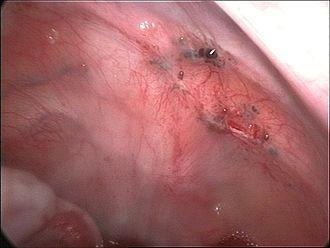

Endometriosis as seen during laparoscopic surgery.

Laparoscopic image of endometriotic lesions at the peritoneum of the pelvic wall.

Laparoscopic image of endometriotic lesions in the Pouch of Douglas and on the right sacrouterine ligament.